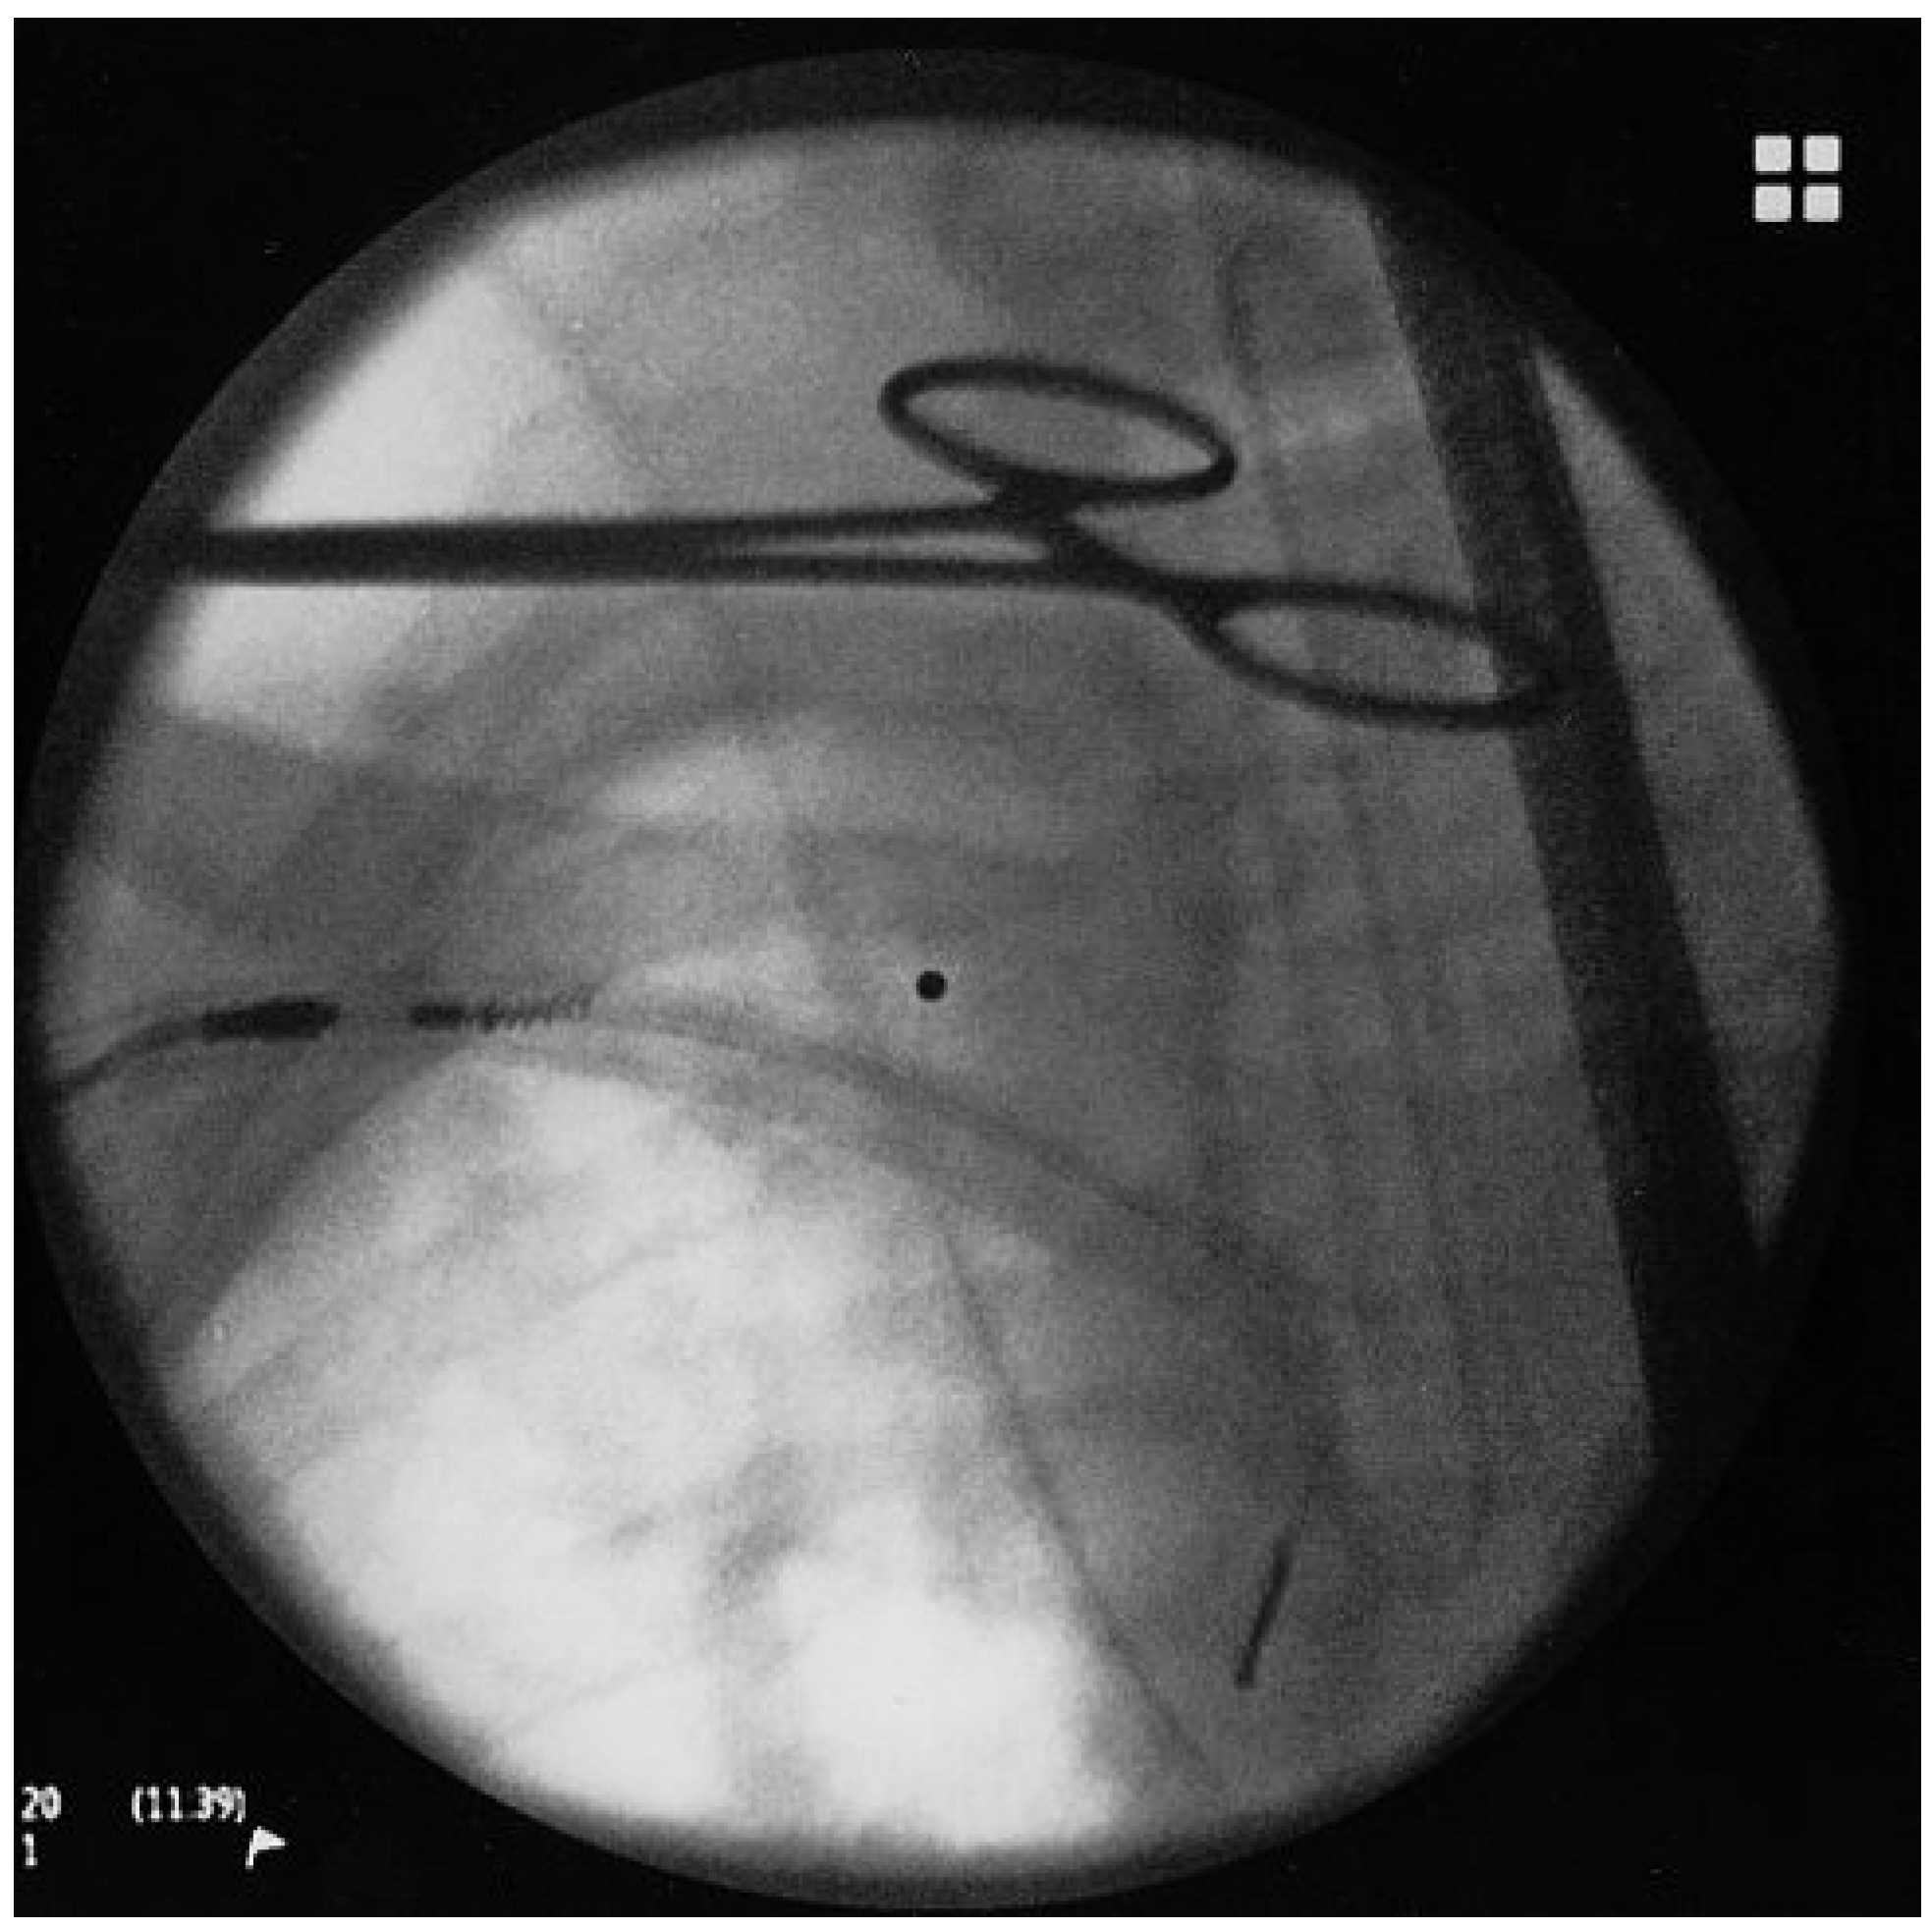

Use of Double Wire Traction for Removal of Pacemaker Leads

Case report